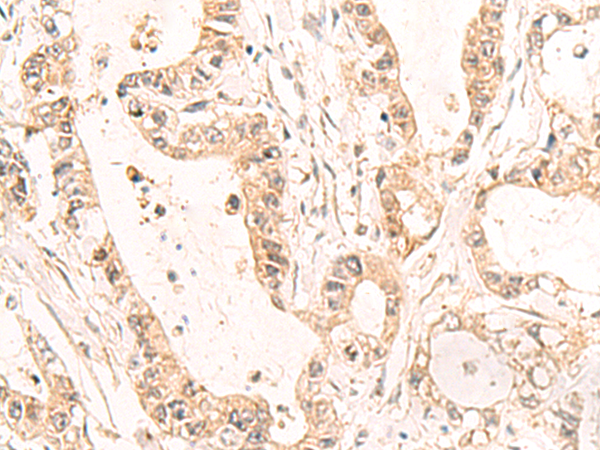

分类: 科研抗体货号: P10112别名: PUS4应用: IHC反应种属: Human, Mouse, Rat